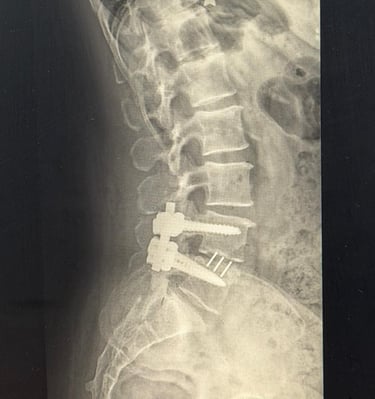

En Let´s Rehab, cada sesión está diseñada en torno a ti, adaptándonos a tus necesidades tras una cirugía o lesión.

Momentos reales de recuperación y cuidado personalizado.